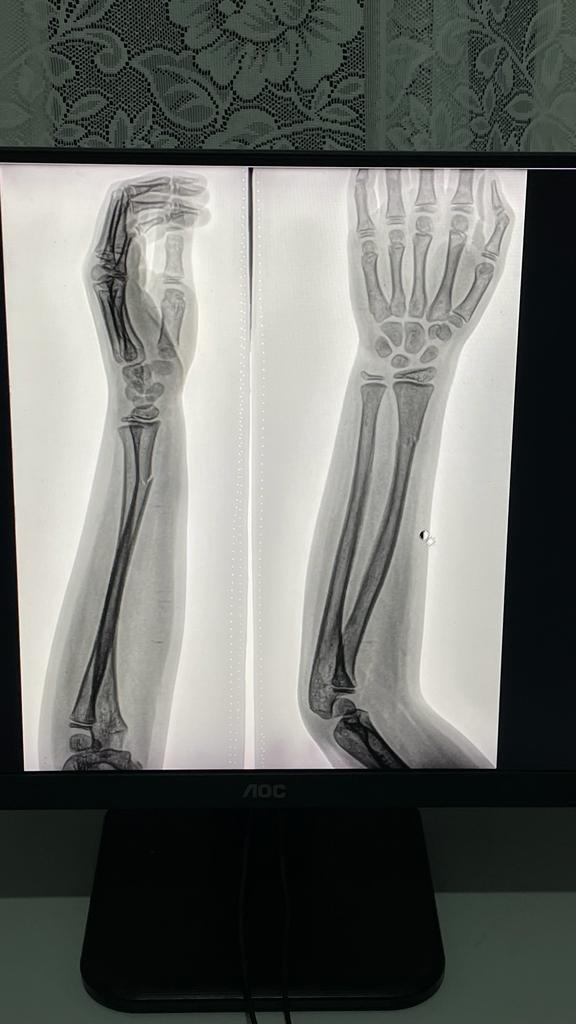

Девочки с Кизляра, посоветуйте хорошего травматолога?! У дочери перелом руки😫гипс поставили , меня что то смущает.